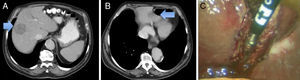

En 3 pacientes el primer tiempo de la cirugía fue realizado por abordaje laparoscópico. En los otros 3 pacientes fue realizado mediante laparotomía por la localización anatómica de las MH. Las características clínicas de los pacientes intervenidos por laparoscopia se presentan en la tabla 1. Todas las resecciones hepáticas fueron realizadas en posición de litotomía Trendelemburg invertido 20°. El abordaje fue mediante 3 trocares, uno de 5mm en el hipocondrio derecho, uno de 11mm en el ombligo y uno de 12mm en el hipocondrio izquierdo. Las cirugías realizadas fueron: 2 resecciones limitadas y una seccionectomía lateral izquierda parcial (fig. 1). Posteriormente se añadieron 2 trocares para efectuar la cirugía colorrectal.